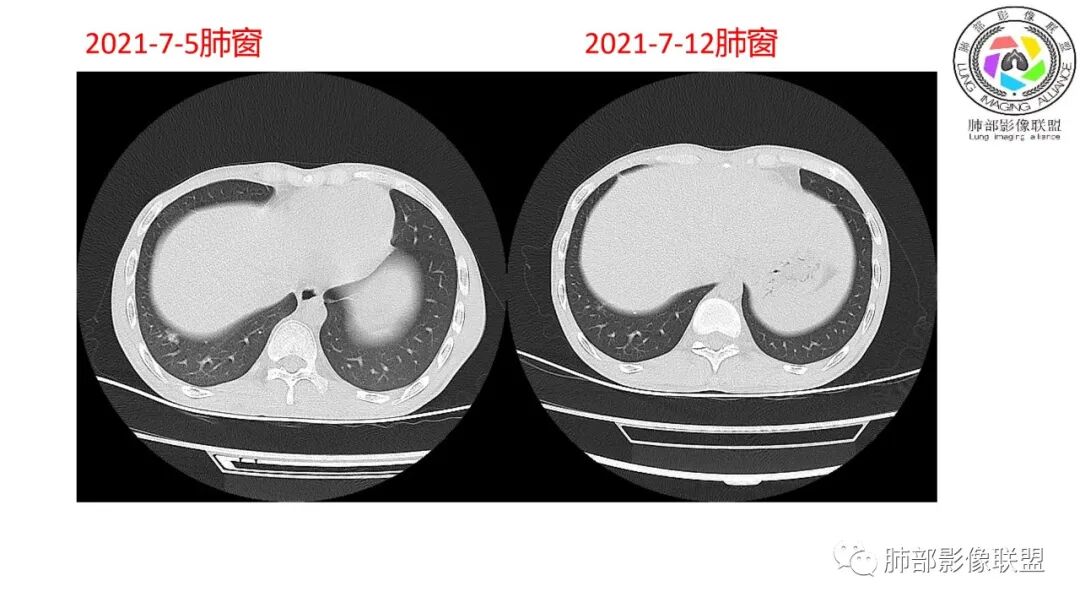

这个影像有啥特点?大家还是读临床

南边:对侧?

南边:12日好一些

南边:支持炎性,结合病史,马尼首选

影像与临床:1.青年男性,HlV阳性,颜面部皮疹(未提供皮疹图像)、发热(高热),实验室CRP、PCT高,T-Spot阴性。2.右肺下叶空洞结节,壁厚不均,边界清楚,其内线状影,未见液平及钙化,未见卫星灶,纵隔淋巴结增大,双侧腋窝见增大淋巴结。心腔内低密度提示贫血可能。肝脾影增大,未见结节影及块影。腹膜后见多发增大淋巴结。